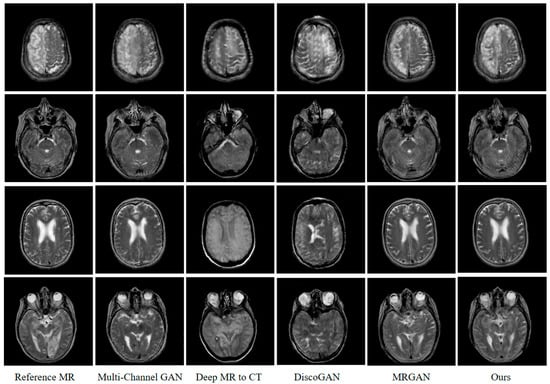

| MAE ↓ | RMSE ↓ | PSNR ↑ | SSIM ↑ | PCC ↑ | Imaging Rate | |

|---|---|---|---|---|---|---|

| Multi-Channel GAN | 23.513 | 26.647 | 68.076 | 0.637 | 0.862 | 25.74 ms |

| Deep MR-to-CT | 21.362 | 40.941 | 64.063 | 0.51 | 0.697 | 51.47 ms |

| DiscoGAN | 19.245 | 37.143 | 64.932 | 0.511 | 0.741 | 22.81 ms |

| MR-GAN | 13.293 | 26.061 | 68.312 | 0.642 | 0.868 | 54.38 ms |

| Ours | 12.981 | 25.532 | 68.519 | 0.652 | 0.872 | 70.51 ms |